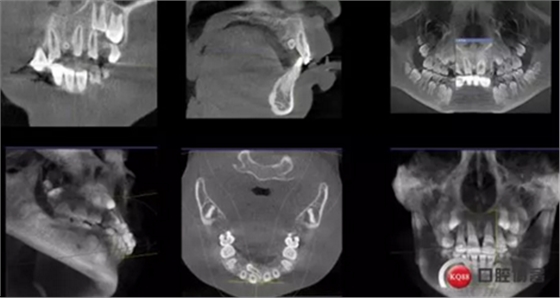

CBCT術(shù)前分析,精準(zhǔn)找到牙齒的具體位置

確定了方案和術(shù)前良好溝通和小孩良好的配合,牙齒很快就拔了出來(lái)。